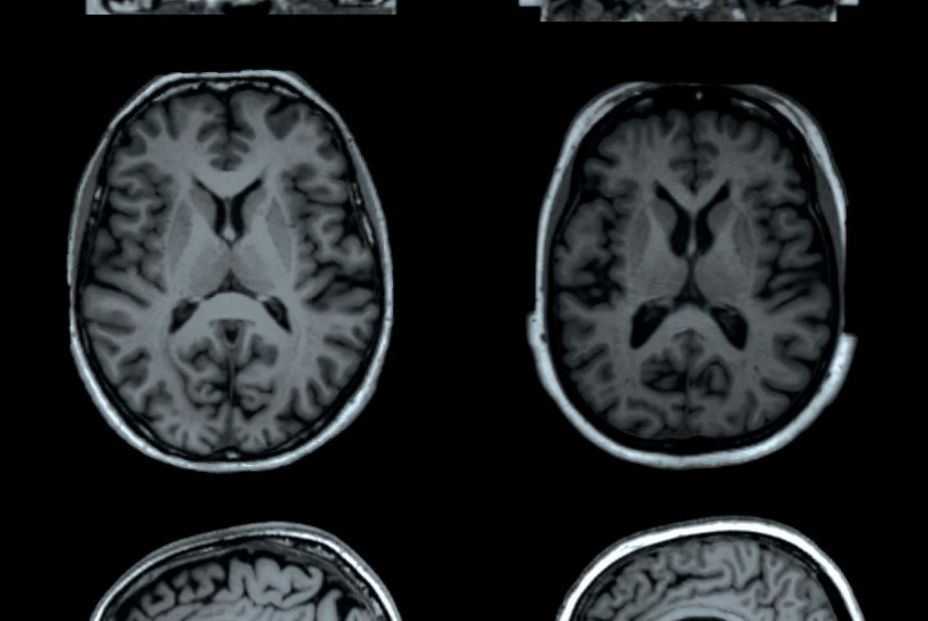

El investigador Daniel Martins-de-Souza, de la Universidad de Campinas (Brasil), y sus colegas utilizaron la resonancia magnética para comparar la estructura cerebral de 81 participantes en el estudio que se recuperaban de una infección leve por COVID-19 y 81 individuos sanos. Los autores descubrieron que el primer grupo presentaba un menor grosor cortical, lo que se correlacionaba con las deficiencias cognitivas y síntomas como la ansiedad y la depresión.

El estudio muestra el espectro del impacto cerebral de la infección por el coronavirus del síndrome respiratorio agudo severo 2 , que va desde las alteraciones a largo plazo en individuos con infección leve (atrofia cortical orbitofrontal, deterioro neurocognitivo, fatiga excesiva y síntomas de ansiedad) hasta el daño agudo severo confirmado en muestras de tejido cerebral extraídas de la región orbitofrontal (mediante acceso transetmoidal endonasal) de individuos fallecidos por COVID-19.